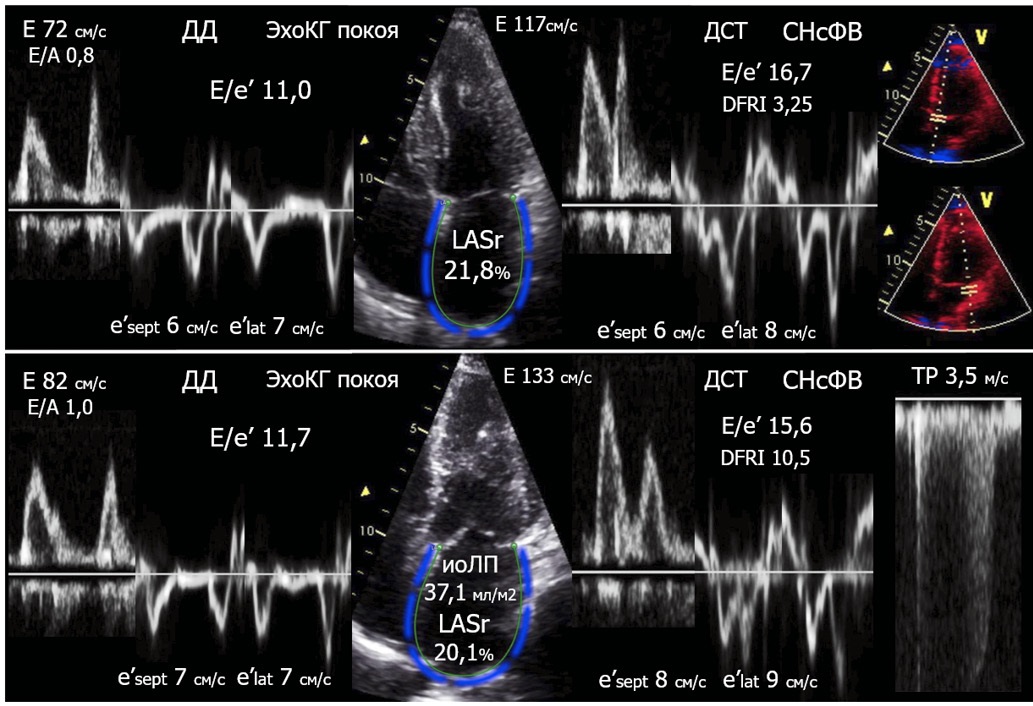

Рекомендации по применению стресс-ЭхоКГ с ВЭМП от EACVI/ASE 2017г содержат исчерпывающее описание особенностей диагностики СНсФВ при проведении ДСТ [8]. Однако отмечено, что реальный клинико-диагностический процесс сопровождается неопределенностью/отсутствием консенсуса относительно универсальных критериев положительной пробы ДСТ [10]. Важно добавить, что именно угнетение ДР ЛЖ — достижение Е/е′ >14 при выполнении ФН — повышает чувствительность определения СНсФВ c 34% до 90%, несколько снижая специфичность — от 83% до 71% в сравнении с традиционной ЭхоКГ покоя (верификация СНсФВ по данным катетеризации правых отделов сердца) [11]. В действующих национальных клинических рекомендациях по хронической сердечной недостаточности (2024) этот критерий предложен впервые, используется как основной и наиболее важный, увеличение Е/е′ >14 считается достаточным для диагностики СНсФВ [6]. Также рекомендовано учитывать увеличение скорости трикуспидальной регургитации как признак проявления ЛГ [6][8]. Согласно нашим данным, в рамках проведения комплексного анализа, вероятно, стоит выделить дополнительные признаки угнетения ДР ЛЖ: DFRI и паттерн наполнения ЛЖ (E>A), которые соответственно позволяют учитывать возможность к растяжению ткани миокарда ЛЖ и распределение наполнения ЛЖ (рис. 3, табл. 4). Указанные особенности при их дальнейшем исследовании, вероятно, можно учитывать для дифференциации вариантов диастолического ответа на дозированную ФН (рис. 3).

Рис. 3. Варианты положительного ДСТ.

Примечание: верхняя панель: достижение E/e’ >14; DFRI значимо <13,5; Е/А=1,0; признаки ЛГ при ФН отсутствуют. Нижняя панель: достижение E/e’ >14; DFRI <13,5; Е/А=1,4; наличие ЛГ при ФН. Цветное изображение доступно в электронной версии журнала.

Сокращения: ДД — диастолическая дисфункция, ДСТ — диастолический стресс-тест, иоЛП — объем левого предсердия, индексированный по площади поверхности тела, СНсФВ — сердечная недостаточность с сохраненной фракцией выброса, ЭхоКГ — эхокардиография, LASr — Left Atrial reservoir Strain (деформация резервуарной фазы левого предсердия).